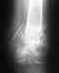

Насчет полной нагрузки - как-то по этим рентгенограммам это чересчур оптимистично.

Причём сказано это было абсолютно уверенно после первого же взгляда на снимки (правда, сначала было высказано несколько отборных крепких слов в адрес оперировавшего...). Может тут повлияло плохое качество репродукции и не всё видно на прикрепленном снимке?

Вот что в итоге получилось, снимки от 13 января 2010 года. В феврале убрали пластину, т.к. были боли в ноге в определенных ситуациях, например, при беге. Хотелось бы, если Вам не сложно, услышать оценку оставшейся деформации,насколько это критично в будущем (сейчас вроде всё ОК). Наверное, пора бы уже и позабыть, но всё ж терзают смутные сомнения, правильно я поступил, что не стал переделывать...Спасибо заранее.

Кликните для загрузки файла 1.jpg

39KB (40508 bytes)